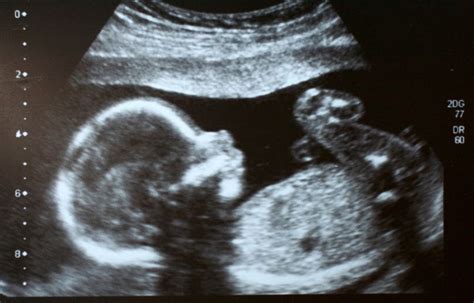

Das Screening 12, auch als Ersttrimesterscreening oder Combined Test bekannt, wird in der Frühschwangerschaft durchgeführt und beinhaltet die Nackenfaltenmessung. Die Nackenfalte ist eine Flüssigkeitsansammlung zwischen der Haut und dem Weichteilgewebe im Nacken des Fetus, die im Ultraschall zwischen der 11. und 14. Schwangerschaftswoche als schwarzer Zwischenraum zu erkennen ist. Durch die Messung der Nackenfalte und die Beurteilung von Zusatzmarkern wie dem Nasenbein, dem Blutfluss im Herzen und herznahen Venen können die Wahrscheinlichkeit von Chromosomenfehlern wie dem Down-Syndrom eingeschätzt und die meisten schwerwiegenden Fehlbildungen entdeckt oder mit hoher Wahrscheinlichkeit ausgeschlossen werden.

Das Organscreening, auch als Screening 22 bezeichnet, wird um die 20. bis 23. Schwangerschaftswoche durchgeführt. Bei dieser detaillierten Ultraschalluntersuchung werden die Organe des Fetus systematisch überprüft, um eventuell vorhandene Hinweiszeichen auf Chromosomenfehler oder strukturelle Auffälligkeiten zu beurteilen. Die meisten schwerwiegenden Fehlbildungen können entdeckt oder mit hoher Wahrscheinlichkeit ausgeschlossen werden. Herzfehler zählen zu den häufigsten angeborenen Fehlbildungen; etwa 8 bis 10 von 1.000 Lebendgeborenen sind davon betroffen.